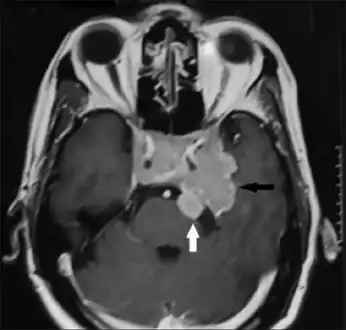

-

Invasive prolactinoma showing invasion into the left temporal lobe -

Prolactinoma on MRI